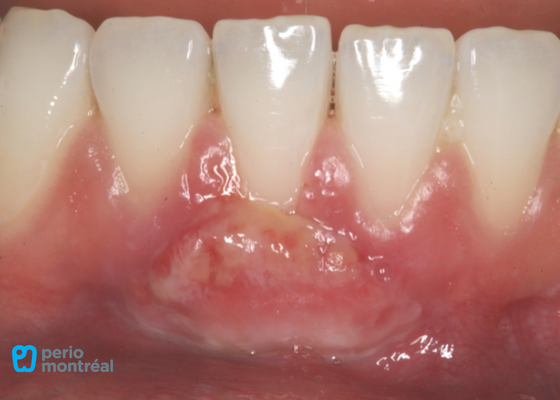

The recipient site is prepared following root planing of tooth #41 to decrease the root convexity. The donor tissue is harvested from the right palate.

Graft Sutured at Recipient Site, Palate Treated with a Hemostatic Agent and Sutured